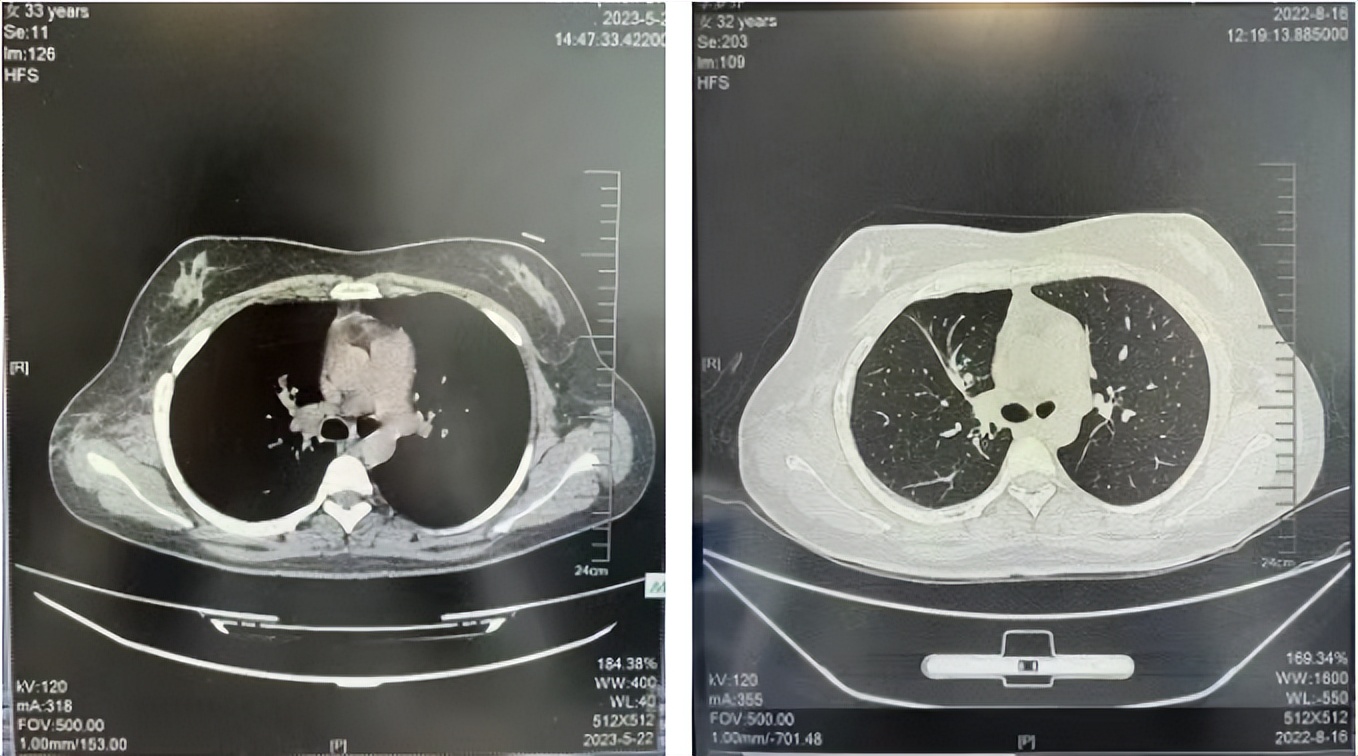

2016年1月复查CT提示支气管截断可见新发小结节,一线治疗采用培美曲塞+DDP方案化疗4周期(培美曲塞3.36,DDP 480mg)。化疗后复查胸部CT:右肺见不规则结节样影,最大层面大小约19mm*8mm,较前比较明显增大,疗效评估PD。2017.3-2017.4予单药多西他赛化疗3周期,疗效评估SD。2018年5月末复查CT提示结节较前增大,评效为PD,2018年6-10月予多西他赛+CBP化疗4周期,疗效评估SD。2022年5月患者出现活动后气短,复查胸部CT示右肺膨胀不良;右侧胸腔积液增多。胸腔积液包埋病理示符合肺腺癌细胞。行NGS基因检测:EML4:exon13-ALK:exon20融合。PD-L1(克隆号22C3)TPS<1%。

临床诊断:右肺上叶恶性肿瘤rT0N0M1a IVA期(第9版分期);恶性胸腔积液。

诊疗经过:2022年5月始口服克唑替尼3个月,出现肝功能异常(DILI 2级伴临床症状),改用恩沙替尼靶向治疗至今,目前评效为维持PR。恩沙替尼应用期间出现轻度肝功能异常(DILI 1级),对症处理后好转。截止目前PFS 33个月。